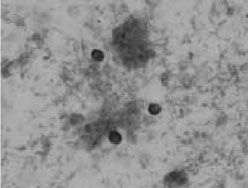

| 【はじめに】 コクシジオイデス症は、真菌であるCoccidioides immitisによる感染症である。この真菌は年間雨量の少ない半砂漠地帯に生息地があり、アメリカ合衆国西南部、メキシコおよび中南米が主な場所である。これらの生息地で感染し、帰国後、発症することから輸入真菌症として扱われ、コクシジオイデス症の他に、ヒストプラズマ症やパラコクシジオイデス症などがある。コクシジオイデス症は4類感染症の扱いを受け保健所への届出義務がある。感染力が非常に強く、健常者にも発症する。発症の危険因子としては高齢者・妊婦・糖尿病・AIDS・喫煙・ステロイド剤投与などである。 【当院で経験したコクシジオイデス症について】 当院でのコクシジオイデス症は、Wegener肉芽腫と診断され、プレドニンなどにより治療されたアメリカ人に発症した。血中(1→3)- -D-グルカン値は治療初期、中期に増加はなく、その後、胸水貯留を認めたときにカットオフ以下での若干の上昇があり、それ以降上昇を続けた。胸水培養からは真菌が発育し主治医に報告した。患者情報として、コクシジオイデス症の発症が見られる地域での在住歴があることを知り、コクシジオイデス症を疑い、真菌医学研究センターに同定を依頼した。菌体からのPCR等でCoccidioides immitisと同定された。また血液培養、喀痰培養においても同様に発育した。今回のコクシジオイデス症患者は、アメリカ(アリゾナ)在住時にCoccidioides immitisの感染を受けており、ステロイド療法により播種性コクシジオイデス症になったと考えられた。 【検査室におけるCoccidioides immitisの対応】 コロニー形態から本菌を推定するのは難しく、生息地への渡航歴などの患者情報から本菌を疑う事になる。本菌は国立感染症研究所による病原体等の危険度分類において、真菌として最高のレベル3に分類され、最も危険度の高い真菌とされる。病原性が強く、培養中に感染可能な分節型分生子を形成する。この分生子は同定操作などによって空気中に飛散し、吸引から肺へ感染する可能性があり、業務感染となる。このようなことからも設備の整った検査室(P3)での取り扱いが必要とされる。しかしP3の設備を備えた検査室はほとんどない。本菌が疑われる場合には、同定操作等をせずに分節型分生子の飛散を防ぐため、シャーレの周りをテープで密封する。その後、専門の施設(千葉大学真菌医学研究センター 病原真菌研究部門)に相談することを進める。ヒトに感染している状態(球状体や内生胞子)からのあらたなヒトへの感染はない。よって患者検体中にもこのような状態で存在する。しかし患者検体は放置することなくすみやかに処理する。これは適当な環境下では発芽して感染可能な分節型分生子を形成するからである。 【まとめ】 感染症検査を進める上で、効率よく原因菌を推定し同定するには、患者情報が必要である。今回の症例でも患者情報からコクシジオイデス症が疑われたことで、早期に原因菌が推定され、業務感染を起こすことなく専門機関での同定に至った。このように感染症検査に必要な患者情報を臨床医から提供してもらう必要がある。これには患者情報から原因菌の推定が可能であった症例を臨床へアピールし、患者情報の大切さを認識してもらうことも一法である。 【当院におけるコクシジオイデス症に対する対応】 当院入院患者からコクシジオイデス症患者が発生したことを受けて、感染症管理治療部・ICTでは下記の暫定マニュアルを作成した。コクシジオイデス症はヒトからヒトへの感染はなく、米国では風土病であり、必ずしも個室入院ではない。しかし、千葉大学医学部附属病院で、本症例を取り扱うことは稀であり、また本症は痰、胸水、血液から菌が分離されたことから、慎重を期すため重装備ではあるが、以下の通りマニュアルを定めた。 1.患者は個室に収容し、手術用マスクを着用する。 2.部屋の外にでることは可能であるが、必ず、マスクを着用する。 3.医療従事者は、原則、手術用マスクを着用する。患者がマスクを着用できない場合は、咳、痰などの呼吸器症状が強い場合は、ガウンを着用し、体液が白衣に付着しないようにする。 4.付き添いの家族は、患者と接する時間が長いのでマスク、ガウンを着用する。 5.喀痰などをふき取ったティッシュは、ビニール袋に入れ一箇所にまとめておく。袋の口を密閉した後、その日の内に感染性廃棄物として廃棄する。 6.尿は頻回に捨てる。廃棄に使用したカップ類は十分に水洗する。全身感染症の場合は、さらに厳重な対応が必要になるのでICTへ相談する。 7.患者の検体を検査部に提出する場合は、主治医が直接届ける。その時、Coccidioides immitisが存在する可能性を口頭で伝える。(検査室内感染を防止するため) 8.患者のベッド周囲は、1日1回、アルコールで清拭する。 9.シーツは2〜3日に一度交換する。使用後はアクアフィルムに入れ、感染性リネンとして処理する。 10.患者の衣類は、病棟で洗濯してもよい。乾燥機にかけ、熱を通すこと。自宅に持ち帰る場合は、ハイターなど次亜塩素酸を含有する漂白剤を使用した後、洗濯する。 11.職員にコクシジオイデス症を疑う症状が出現した場合は、感染症管理治療部に連絡し、対応を相談する。 |